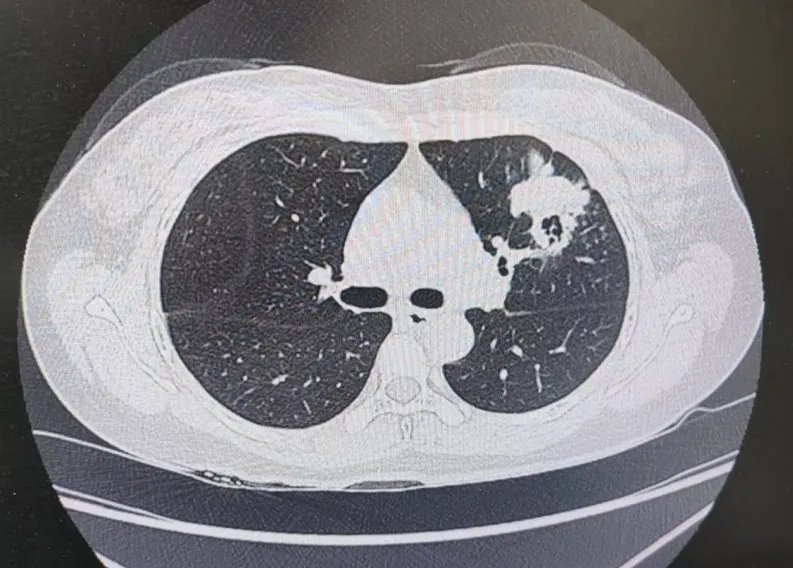

患者肺部CT影像

“一般來說,肺炎經(jīng)過一周的抗感染治療,病灶會有所吸收。但陳女士的肺部陰影紋絲不動,這種情況必須提高警惕。”宋剛主任團隊立即啟動了更深入的“三部精準診斷”程序:

3、CT引導(dǎo)下穿刺活檢:病理診斷為左肺上葉腺癌。

肺炎型肺癌,因其影像學(xué)表現(xiàn)與普通肺炎極為相似,臨床上誤診率極高。然而確診僅是第一步。宋剛主任當天即召集腫瘤科、病理科、影像科等多學(xué)科專家會診,為陳女士制定個體化治療方案。